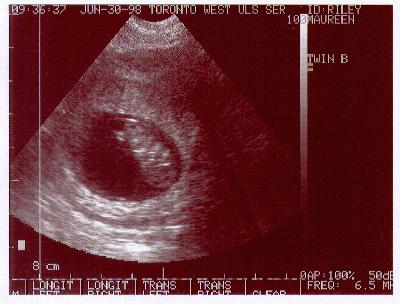

Twin "B"

This is the first "good" ultrasound of "Boris" (Twin "B").

As in the previous image of "Abigail" I really have no clue what

you are looking at! I think the technician said the head was at the bottom

and the body was above that (i.e. taking a dive!)

Again, a good Heartbeat was seen, and the doctor says this baby

is also a good size. |